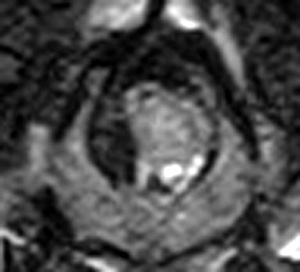

市外の先生からフレブルちゃん両後肢麻痺グレード3でMRI検査及び手術依頼でご紹介がありました。MRI検査で第12‐13胸椎間椎間椎間板ヘルニア、右側優位な圧迫と診断し手術となりました。